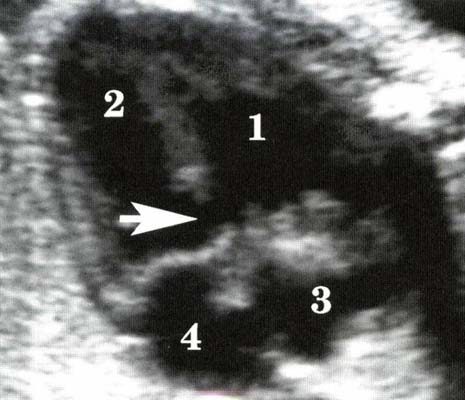

*Maladie d’Ebstein : Dilatation tricuspide + fuite tricuspide

- Déplacement du feuillet septal de la valve tricuspide vers l’apex du VD

- Souvent associés à des anomalies morphologiques des feuillets valvulaires et à une insuffisance tricuspide de sévérité variable.

- Dilatation OD + parfois dilatation VD (due à la fuite valvulaire)

Maladie d’Ebstein et dysplasie valvulaire tricuspide peuvent s’accompagner in utero d’une cardiomégalie, d’une anasarque et de troubles du rythme.

Leur diagnostic est facile si coexiste une dilatation majeure de l’OD et une fuite tricuspide importante.